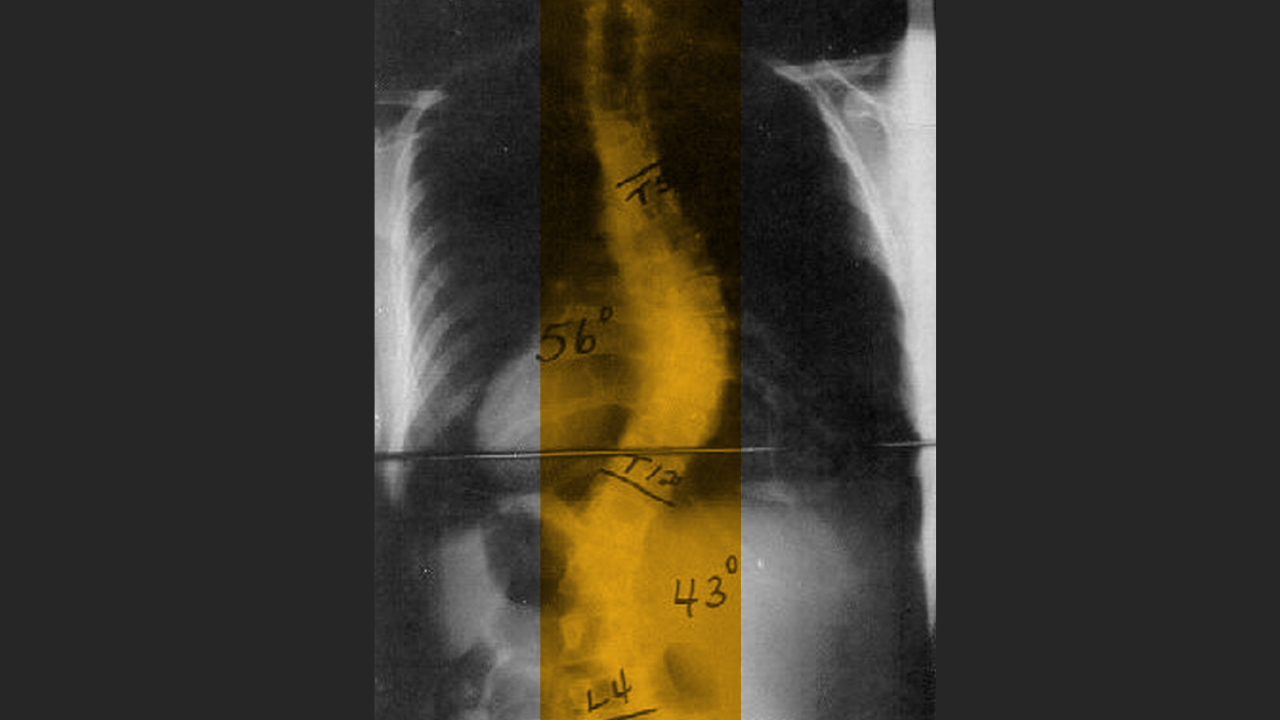

AIS is one of the most common forms of scoliosis, causing spinal deformity in 1 to 3% of adolescents. Dr. Hadley-Miller says that while the disease is not fatal, its impacts — financial, social, physical and emotional — are devastating for kids and families.